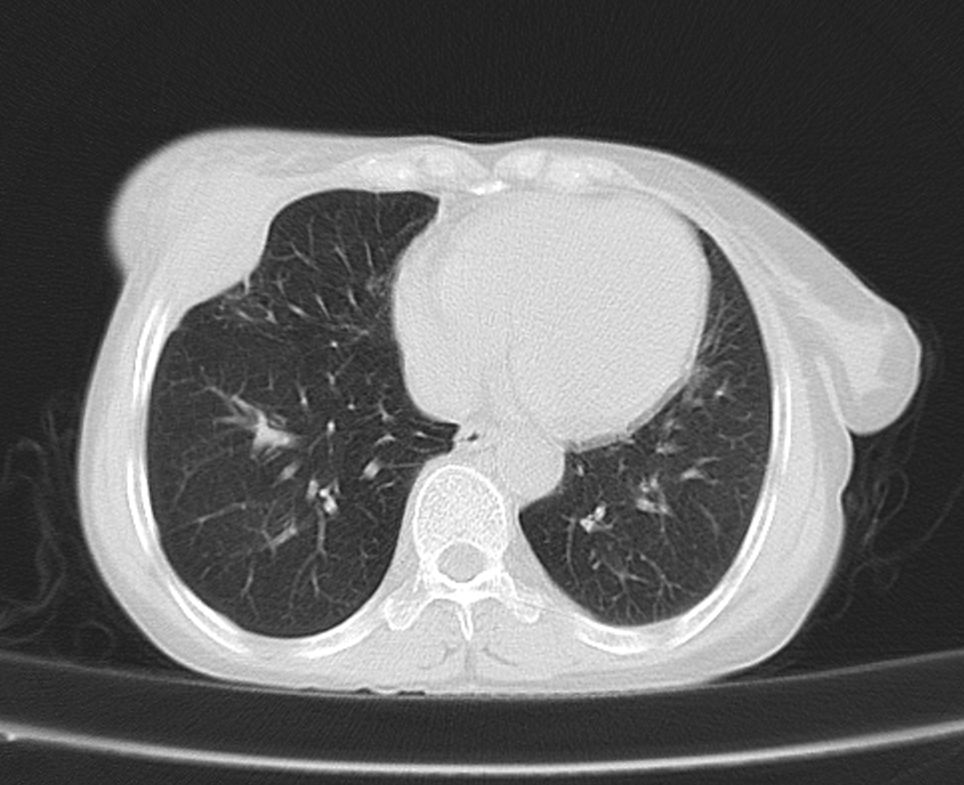

标题: CT21609:右乳包块1年,请各位讨论分析一下,乳腺CA, [打印本页]

标题: CT21609:右乳包块1年,请各位讨论分析一下,乳腺CA,

考虑---右乳癌并胸壁、肋骨、双肺转移。

考虑乳腺癌侵犯肋骨、胸壁及两肺转移可能性大。

右乳癌并胸壁、肋骨、双肺转移。

考虑右侧乳腺癌侵犯肋骨、胸壁及两肺转移。

支持考虑---右乳癌并胸壁、肋骨、双肺转移。

考虑右侧乳腺癌侵犯肋骨、胸壁及两肺转移可能。

考虑右侧乳癌并胸壁、肋骨及双肺多发性转移。